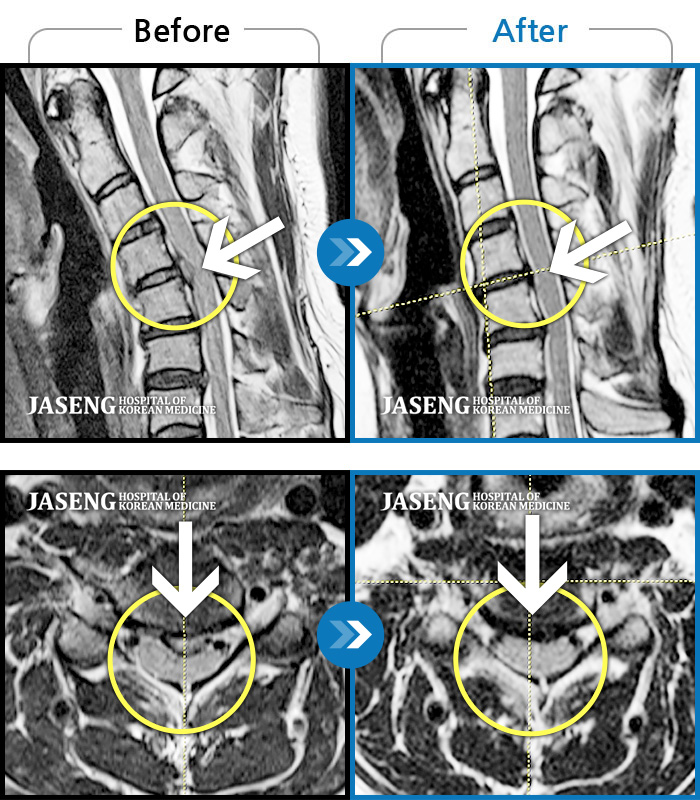

Before

After

환자에게 사전 동의를 받아 동일 조건에서 촬영되었습니다.

개인에 따라 치료 후 부작용이 발생할 수 있으니 의료진과 상담 후 치료를 진행하시기 바랍니다.

허리통증 및 우측 하지 방사통, 풋드랍 진행